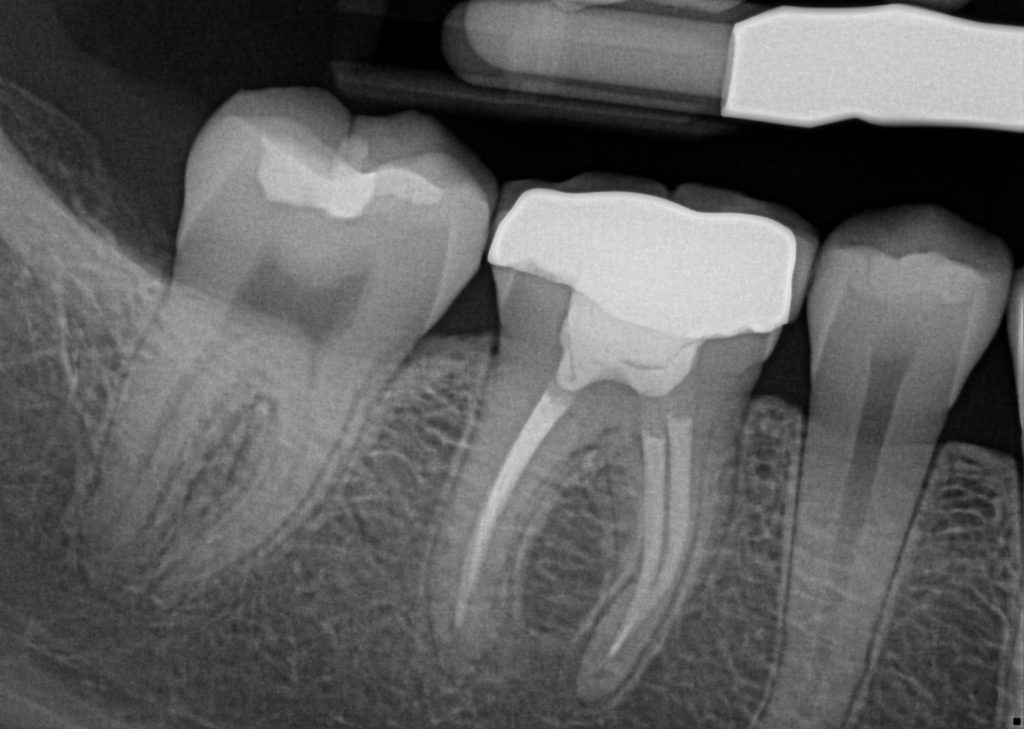

CHECK OUT THIS BEFORE AND AFTER CASE

Pre-Op Root Canal

Post-Op Root Canal